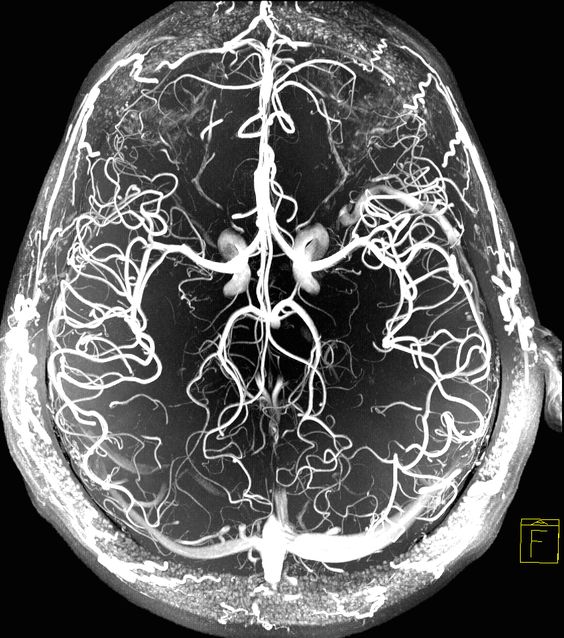

Это один из современных диагностических методов исследования сосудов головы, головного мозга, позволяющий с высокой достоверностью выявить имеющиеся патологии, определить объём функциональности внутречерепной кровеносной системы.

Магнитно-резонансная томограмма сосудистой системы головы, головного мозга и шеи позволяет досконально изучить любые участки ведущих структур, ствола при помощи полученного двухмерного, трехмерного отчетливого изображения. Таким образом, высокая точность и эффективность такого инновационного метода диагностирования позволяет поставить диагноз на самых ранних стадиях проявления недуга.

Что показывает МРТ вен и артерий головного мозга, и что может увидеть врач-рентгенолог на полученном снимке:

- рассмотреть структуру артерии, вены на всей её протяженности, не оказывая при этом вреда человеческому организму;

- оценить происходящие в тканях головы различные биологические процессы;

- физиологические, анатомические характеристики артерий и вен головы;

- четкое отображение сосудов головы в обследуемой области для оценки патологического процесса, дальнейшей лечебной тактики;

- узнать локализацию имеющихся патологических участков, артерио-венозных фистул, гематом, тромбообразований или аневризмов.

Оценка состояния кровеносной системы головы совсем недавно еще считалась чем-то непостежимым. Если просмотреть различные опухолевидные образования, кисты позволял рентген-аппарат, то показать сосудистые патологии он просто не способен, а узи сосудов головы - метод далеко не информативный. Появление магнитно-резонансной томографии — это своеобразный прорыв в сфере диагностики артерий, вен головы, шеи, только такой вид диагностирования помогает изучить коронарную сосудистую сеть - МР ангиография. В этом и заключается важность МРТ диагностики.

МРТ сосудов головы и шеи проводят на специальном аппарате-томографе, действие и работа которого построена на физических явлениях магнитного резонанса при наличии внешнего магнитного поля, для подробного, полного изучения внутричерепной кровеносной системы.

- МР-ангиография — это изучение в совокупности артерий, вен головы, позволяет исследовать особенности состояния, строения и функционирования кровеносной системы мозга.

Если имеется необходимость, например, проведенное магнитно-резонансное исследование сосудов головы не предоставило четкого представления клинической картины, прибегают к контрастному МРТ сосудов головы. В качестве контрастного вещества подбирается специальный раствор с малотоксичными составляющими, хорошо переносимый человеком. Контраст вводят внутривенно, а затем он заполняет сосудистые, жидкостные структуры мозга.

Многие рентгенологи рекомендуют проводить МРТ головного мозга с сосудистой программой, т.к. сосудистый режим позволяет изучать не только различные ведущие отделы, но и все сосудистые сплетения головы, жидкостные резервуары. Это помогает доктору в понимании клинической картины, выставлении достоверного диагноза.

На заключительном этапе расшифровки рентгенолог получает детальные изображения с отображением сосудов головы и шеи, что в дальнейшем лечащему доктору помогает в поиске и назначении упешного лечения.